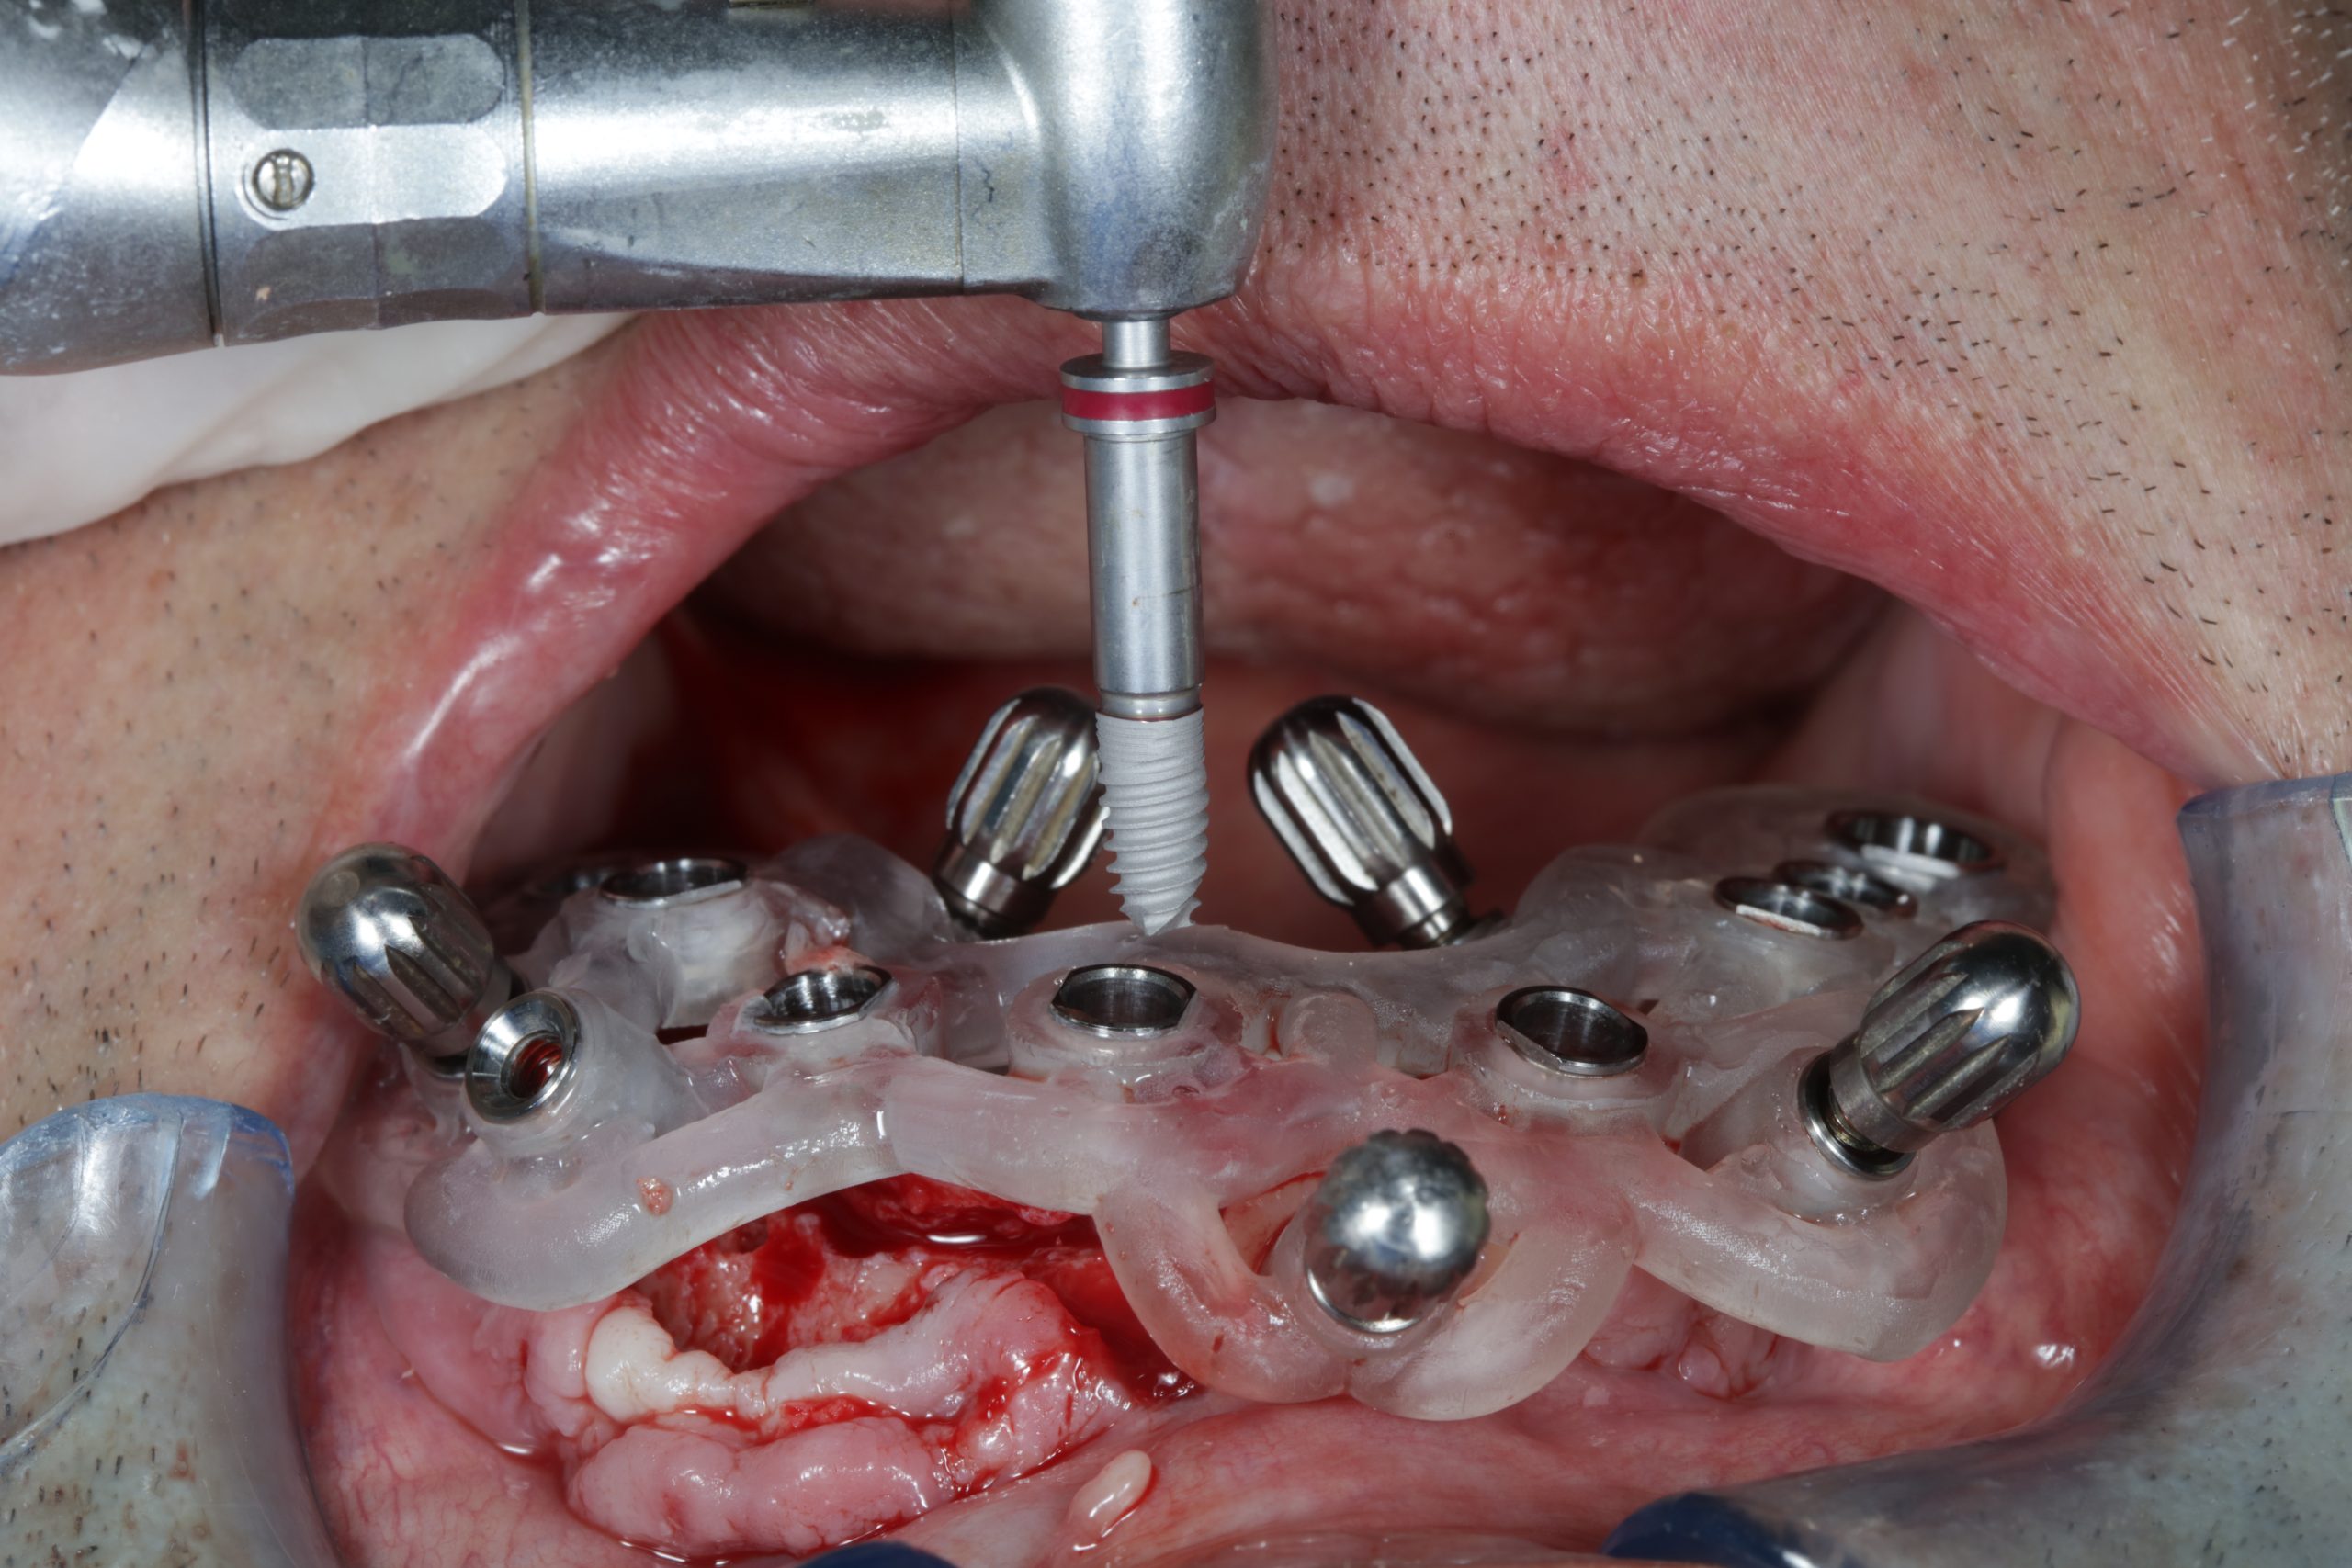

Complete Digital Patient (CDP): guided surgery for complete upper and lower rehabilitation with zirconia-ceramic screw-retained implants

Complete Digital Patient (CDP): the use of guided surgery for implant restoration in total upper and lower rehabilitation with titanium bars and different types of zirconia-ceramic

The use of CDP (Complete Digital Patient) as a basis for planning in a case of complete implant rehabilitation with a full arch in zirconia – ceramicised